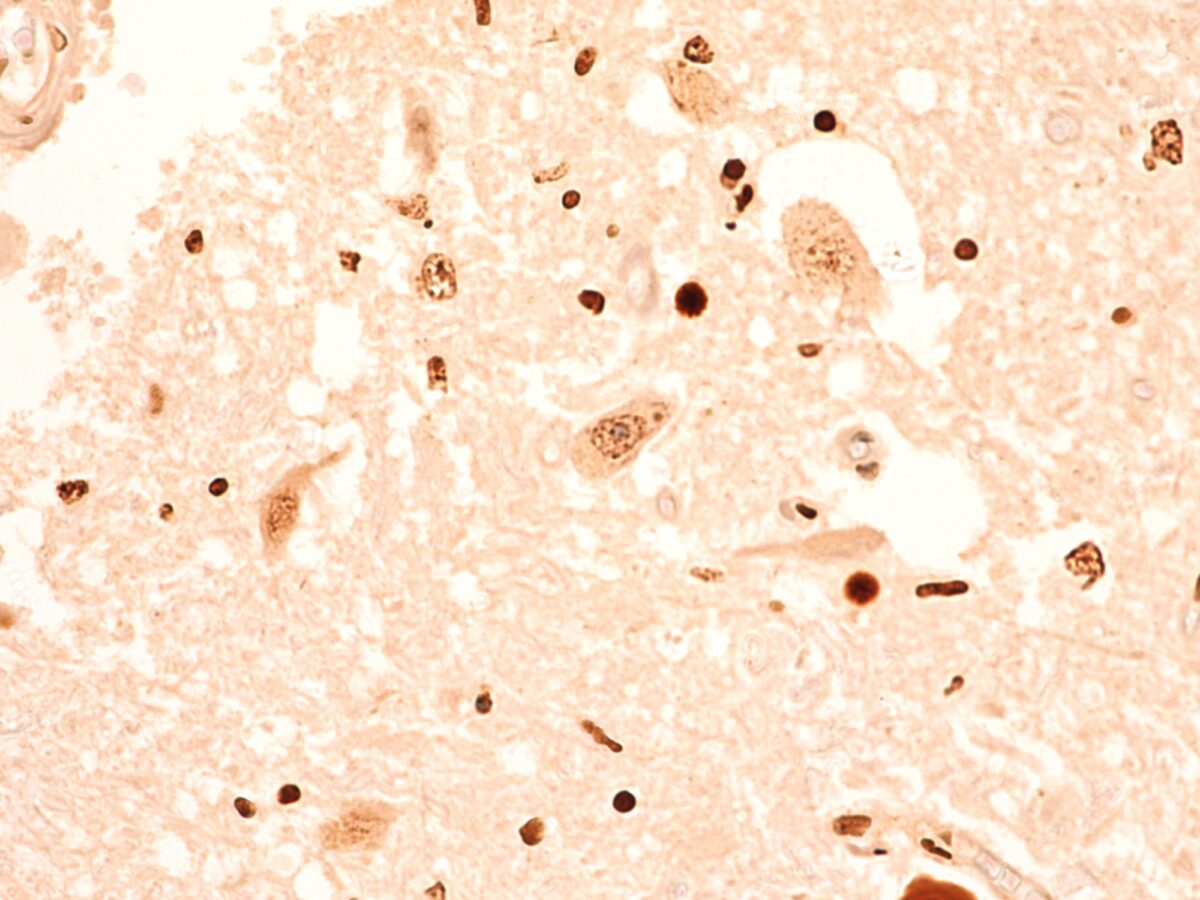

In a new study, the novel TDP-43 RNA aptamer identified damaged cell proteins in brain tissue samples before the cells malfunctioned, which is when symptoms would start to appear, and current tools pick up the disease.

This tool ‘targets’ the disease protein and allows us to see where toxic clumps are building up in the body. It can do this for much lower amounts of disease proteins, and with greater accuracy than ever before.

A new detection method for amyotrophic lateral sclerosis (ALS) and frontotemporal dementia (FTD) using single-stranded RNA aptamers to selectively detect TDP-43 protein aggregates.